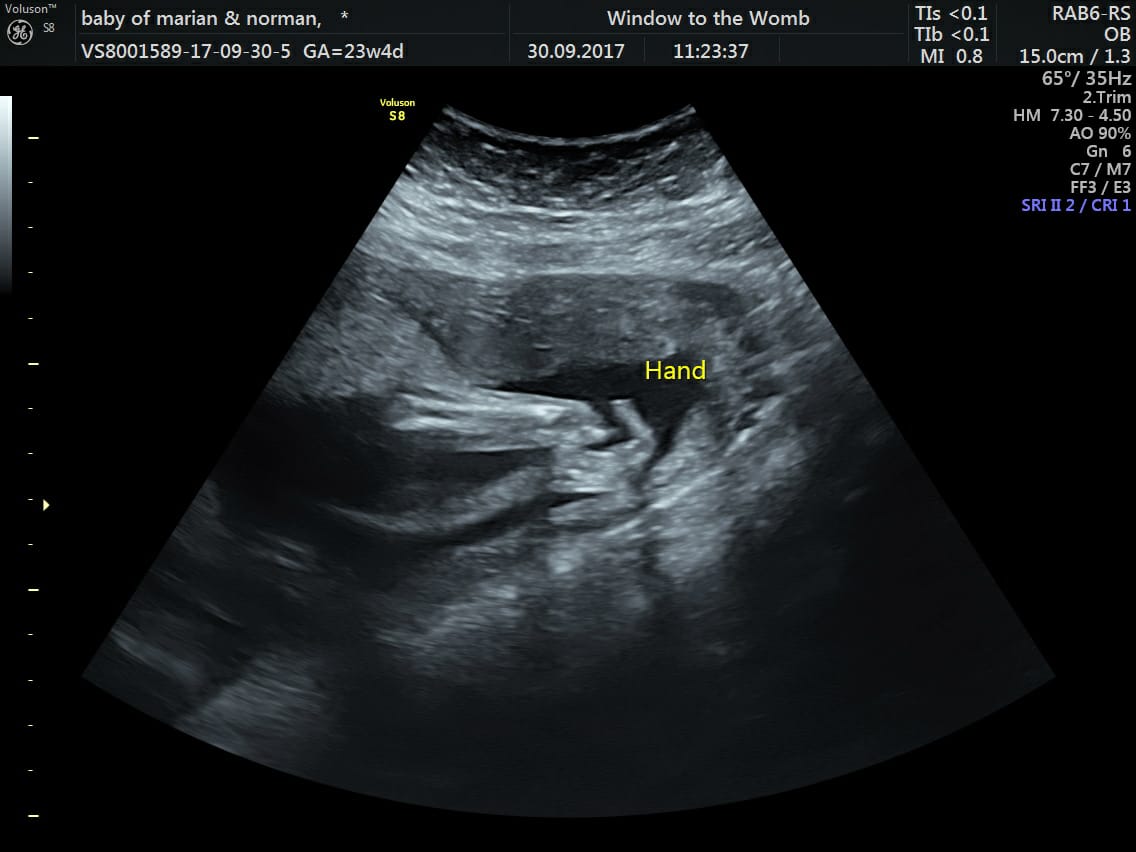

Amazing Story of Baby Jack; Born With One Hand | Window to the Womb

Amazing Story of Baby Jack; Born With One Hand Say Hello to Baby Jack…The Gorgeous Baba We Scanned At Our Belfast Clinic! We recently welcomed